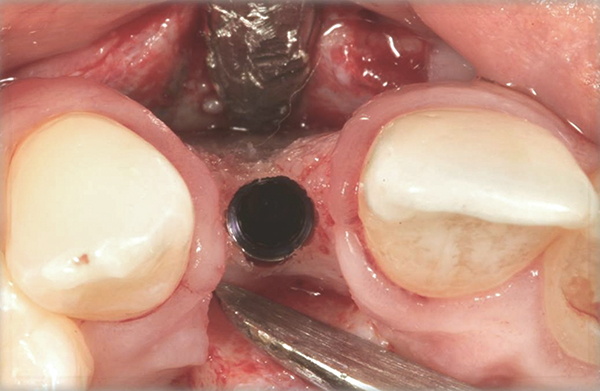

Fig 14. Implant placed into the thin ridge of bone, occlusal view.

Fig 15. A temporary abutment and crown were inserted. A bone graft was then placed on the buccal aspect to augment the thin buccal bony plate.